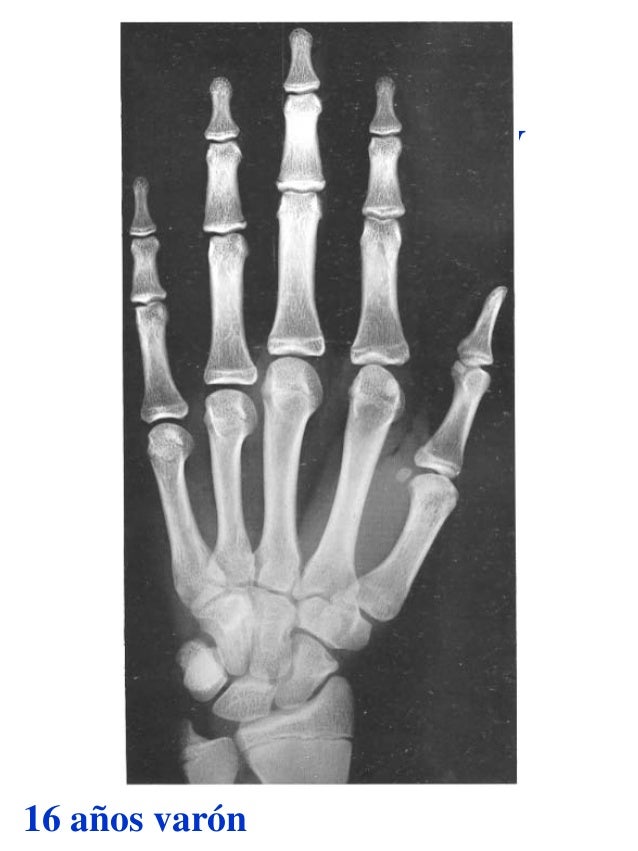

Figura 2 Imágenes de radiografías de mano y muñeca izquierda del

Figura 2 Imágenes de radiografías de mano y muñeca izquierda del Tablas De Greulich Y Pyle Edad Osea The greulich and pyle atlas is used to estimate the age of children and adolescents. El método de greulich y pyle(1) es un método simple de valoración de la edad ósea en pacientes pediátricos. El diagnóstico y la clasificación se basan en el examen físico, el análisis del crecimiento, la maduración ósea, la ecografía de útero y gónadas, y los. Tablas De Greulich Y Pyle Edad Osea.